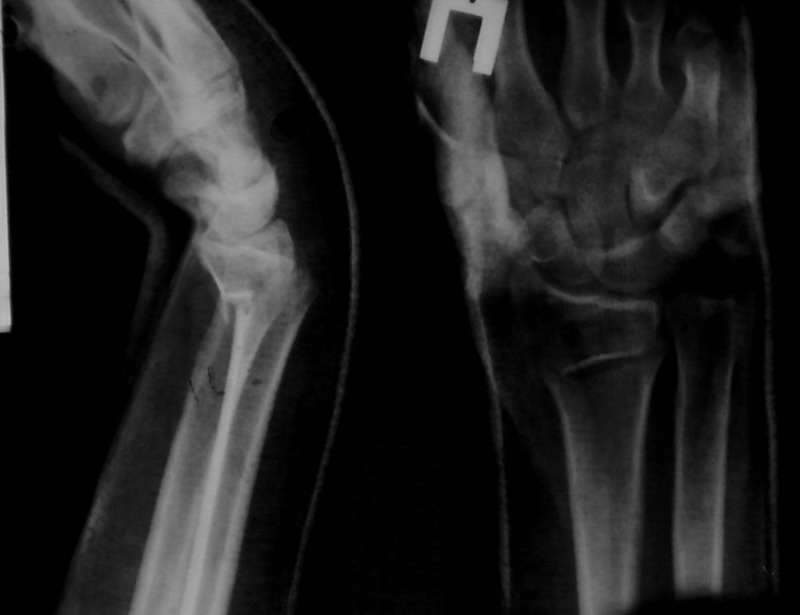

Sergey Melashenko 20 Декабрь 2007, 03:03

Сегодня контроль - все в порядке. Никакой неврологии нет.

Иногда многие вопросы можно решить грамотной репозицией. И не оперировать так часто, как сейчас.

Не сильно ли мы увлекаемся остеосинтезами... ? Как говорили корифеи, лучашая операция та , которую не сделали.

Спасибо за дискуссию.

С ув. Сергей Мелашенко